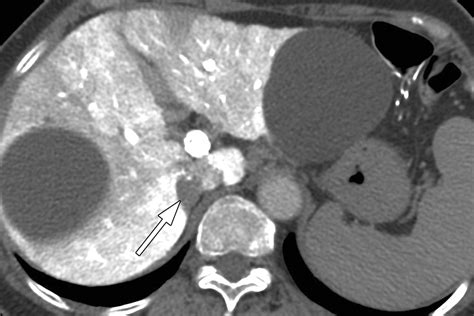

• Imaging Tests: Computed tomography (CT) scans and magnetic resonance imaging (MRI) are commonly used to visualize the adrenal glands and detect tumors. These tests can provide detailed images of the adrenal glands and help determine the size and characteristics of the tumor.